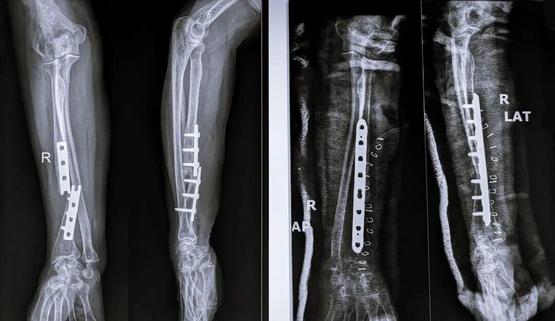

在传统手术疗法中,往往需要将骨块复位后,再使用钢板、螺钉等将其固定,听上去就令人头皮发麻。

打完钢板、螺钉后的骨头丨图虫创意

而且,有部分骨折并不是打完钢板钢钉就一劳永逸,还需要二次手术取出内固定物,这更是增加了患者的痛苦。如何提供更有效、微创的治疗方案,成为该领域最具挑战性的问题之一。